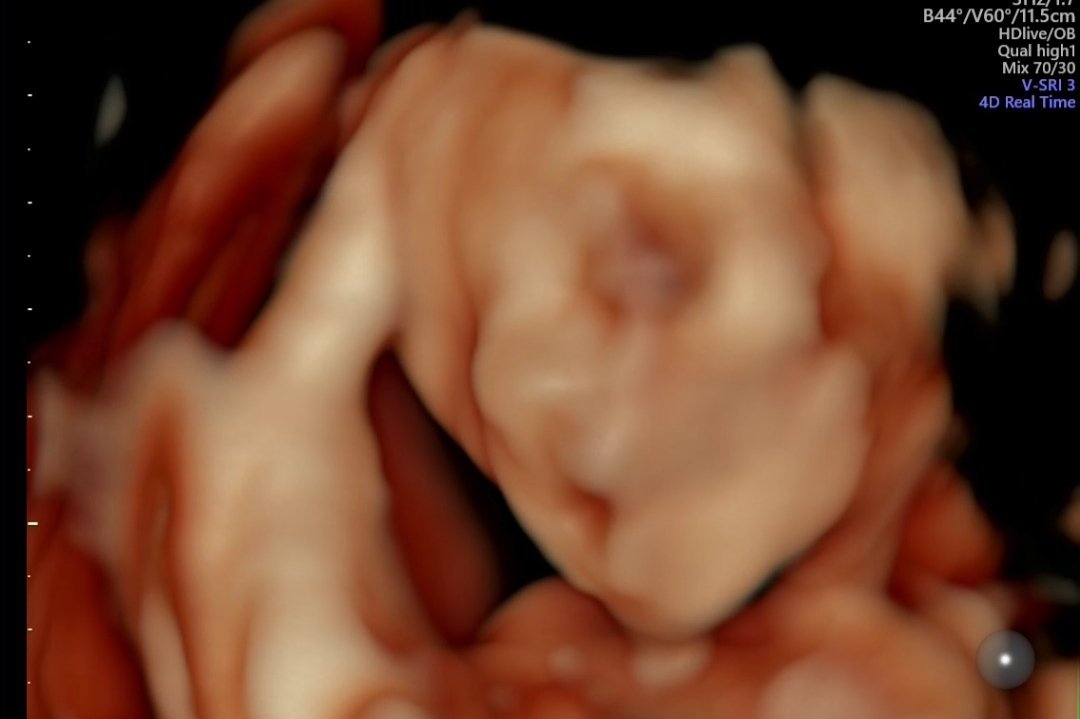

Ето от мен едно зяпнало момиченце. Всичко ѝ е в норма, и няма нищо притеснително, а моите изследвания определи като чудесни.